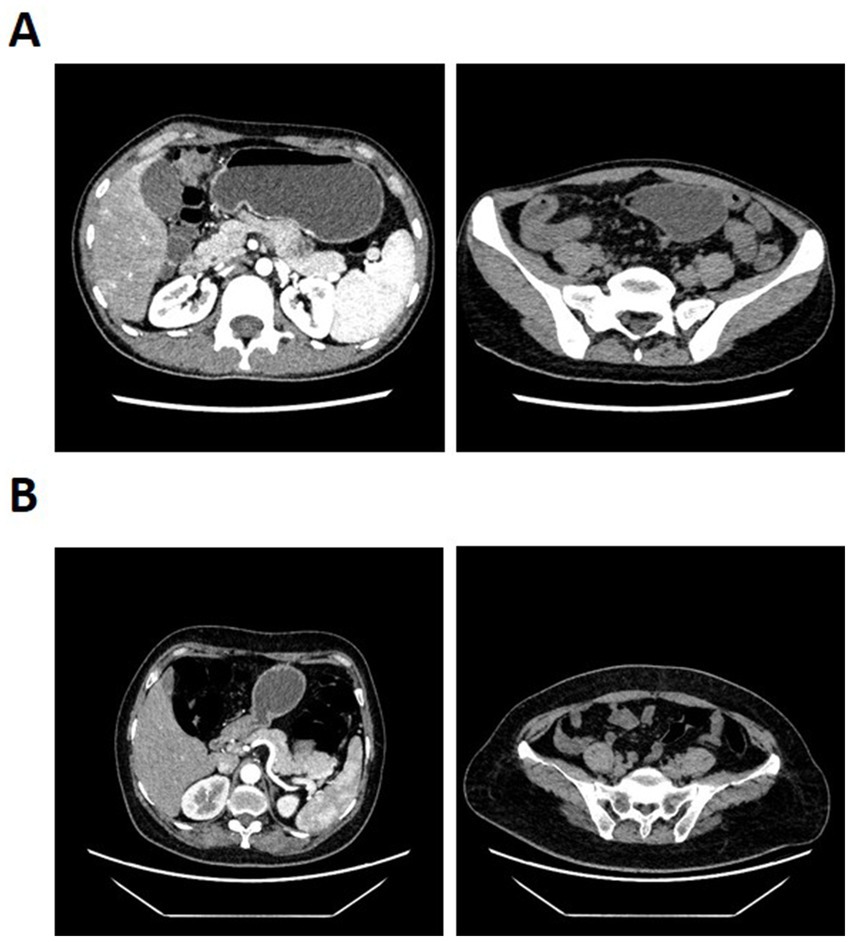

The 120 kVP images with a slice thickness of 1 mm were obtained after inputting the raw data into the post-processing workstation. The virtual monoenergetic images with computational fusion were also obtained under the dual energy Mono+ mode (40–90 KeV) with the slice thickness of 1 mm. The cross-sectional images with a slice thickness of 3 mm and a slice gap of 3 mm were reconstructed for the above images. Two radiologists, each with over 10 years of experience and blinded to patient information, delineated the vessels. This was reviewed by a specialist with over 20 years of experience in abdominal imaging diagnosis. The robustness assessment was conducted in cases with anatomical variability or disease-induced deformation by evaluating the ability of the model in visualizing major vascular variants compared to the expected anatomical course based on CT images. The vessels delineated in consensus by radiologists were referred to as the ground truth. Figure 1 shows the example of CT images from a CD patient and a healthy control individual.

Figure 1. Computed tomography enterography (CTE) images from (A) a CD patient and (B) a healthy control individual.